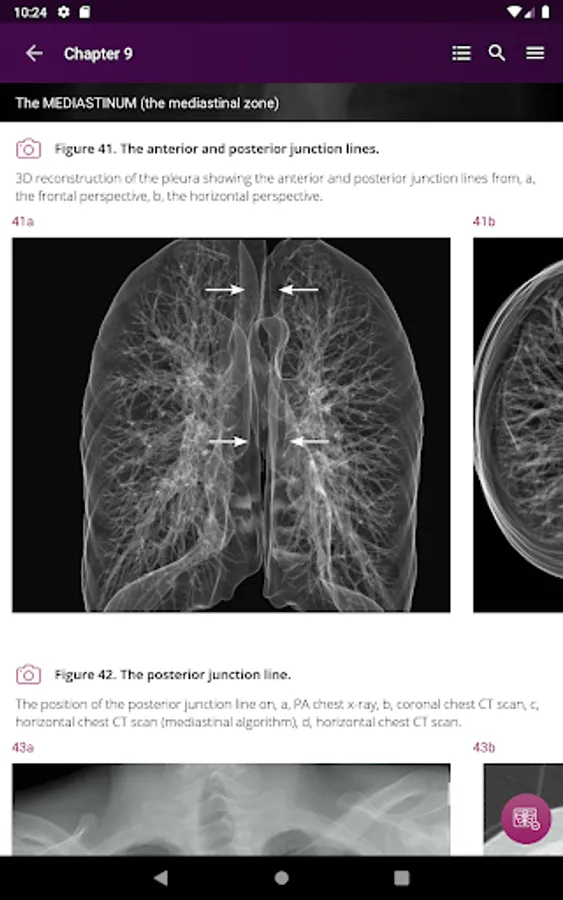

Section II* introduces the concept of radiological zones to give you a starting point in the understanding of the radiological anatomy of the chest. The next chapters review in detail the radiological anatomy of specific anatomical structures, also provide examples of how the x-ray image can change due to pathology. The final chapter explains how the individual structures come together to form the radiological image.